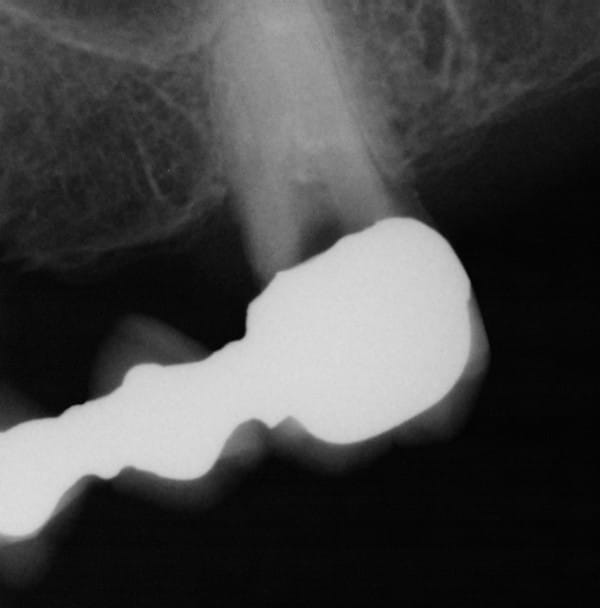

Ceci est un exemple de traitement de poches par photo-ablation en une seule séance en mode continu sans contact, cette technique diffère des traitements par lasers fibrés.

Après sondage et traitement médical, la gencive non attachée est volatilisée avec stérilisation et hémostase immédiate. La cicatrisation est rapide et la ré-attache se réalise en quelques jours, laissant dégagés les espaces biologiques afin de permettre un entretien aisé par le patient, la texture de la gencive prenant un aspect en peau d'orange et reformant progressivement un feston.